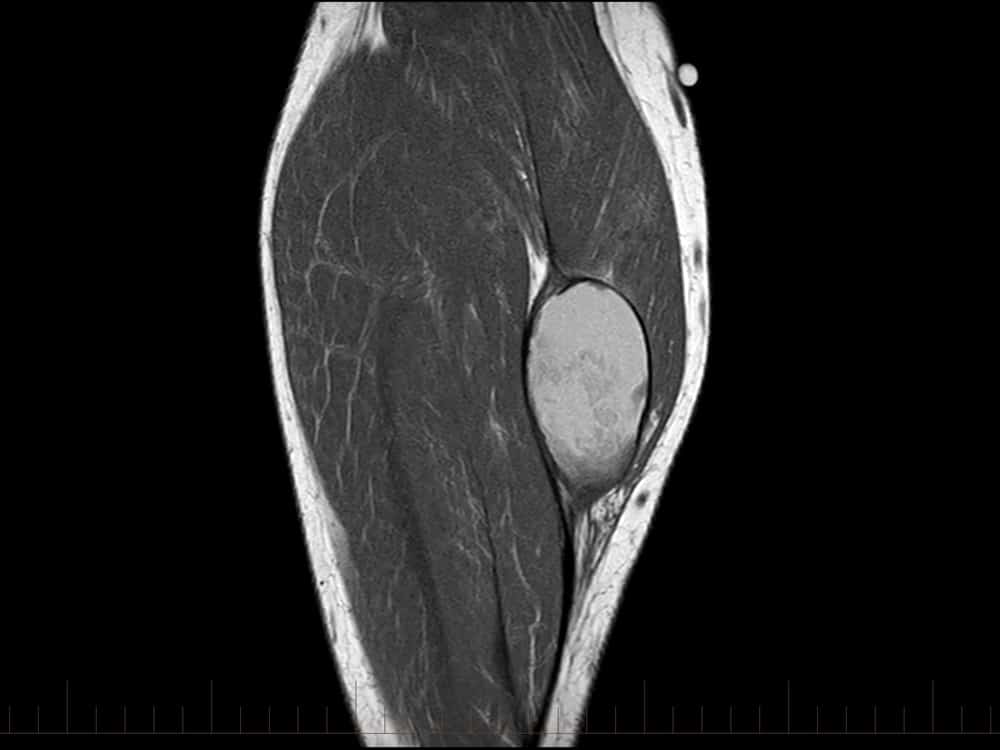

Tụ máu cẳng chân

» Thông tin: Nam giới – 41 tuổi.

» Lâm sàng: Sưng đau cẳng chân / Chấn thương cẳng chân 15 năm.